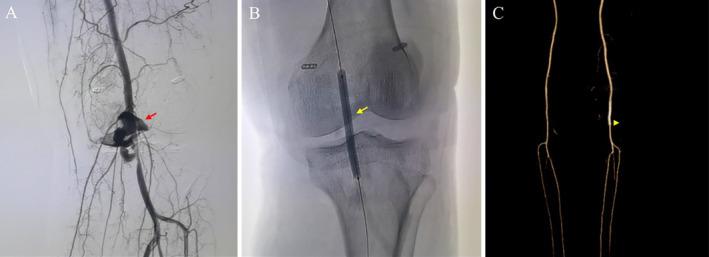

Among the 17,000 knee arthroscopic procedures analyzed, 10 patients were identified with popliteal artery injury (0.059%). The surgeries performed included arthroscopic cystectomy for popliteal cysts, cruciate ligament reconstruction, and posterior horn of the lateral meniscus repair. Treatments for popliteal artery injury included percutaneous intravascular stent implantation (one patient), direct suture repair (four patients), allograft vascular transplantation (one patient), and reconstruction with an autogenous greater saphenous vein (four patients). After a mean follow-up time of 43.1 ± 13.23 months (ranging from 22 to 58 months), no complications were reported. Compared with patients at 1 month after surgery, patients at 2 years after surgery presented improved knee function and ROM. The average Lysholm score increased significantly from 13.8 ± 4.21 to 68.2 ± 15.50, the IKDC score increased from 11.6 ± 2.46 to 48.1 ± 11.75, and the VascuQoL score improved from 54.8 ± 9.54 to 92.5 ± 15.90. Knee extension improved from 13.3° ± 2.36° to 3.5° ± 4.12°, and knee flexion increased from 49.5° ± 12.57° to 107° ± 21.63°. All patients successfully resumed daily activities postoperatively.

在分析的17000例膝关节镜手术中,有10例患者被诊断为腘动脉损伤(0.059%)。所进行的手术包括腘窝囊肿的关节镜下囊肿切除术、交叉韧带重建术和外侧半月板后角修复术。腘动脉损伤的治疗方法包括经皮血管内支架植入术(1例患者)、直接缝合修复术(4例患者)、同种异体血管移植术(1例患者)和自体大隐静脉重建术(4例患者)。平均随访时间为43.1±13.23个月(22至58个月),未报告并发症。与术后1个月的患者相比,术后2年的患者膝关节功能和ROM有所改善。Lysholm平均评分从13.8±4.21显著提高到68.2±15.50,IKDC评分从11.6±2.46提高到48.1±11.75,VascuQoL评分从54.8±9.54提高到92.5±15.90。膝关节伸展从13.3°±2.36°改善到3.5°±4.12°,膝关节屈曲从49.5°±12.57°增加到107°±21.63°。所有患者术后均成功恢复日常活动。